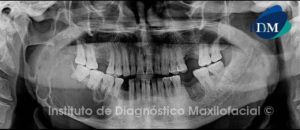

Paciente de sexo femenino y de 59 años de edad es referida al Instituto de Diagnóstico Maxilofacial para realizar el estudio de evaluación ósea para la colocación de implantes, lo cual llamo nuestra atención la presencia de un hallazgo radiográfico en el maxilar inferior.